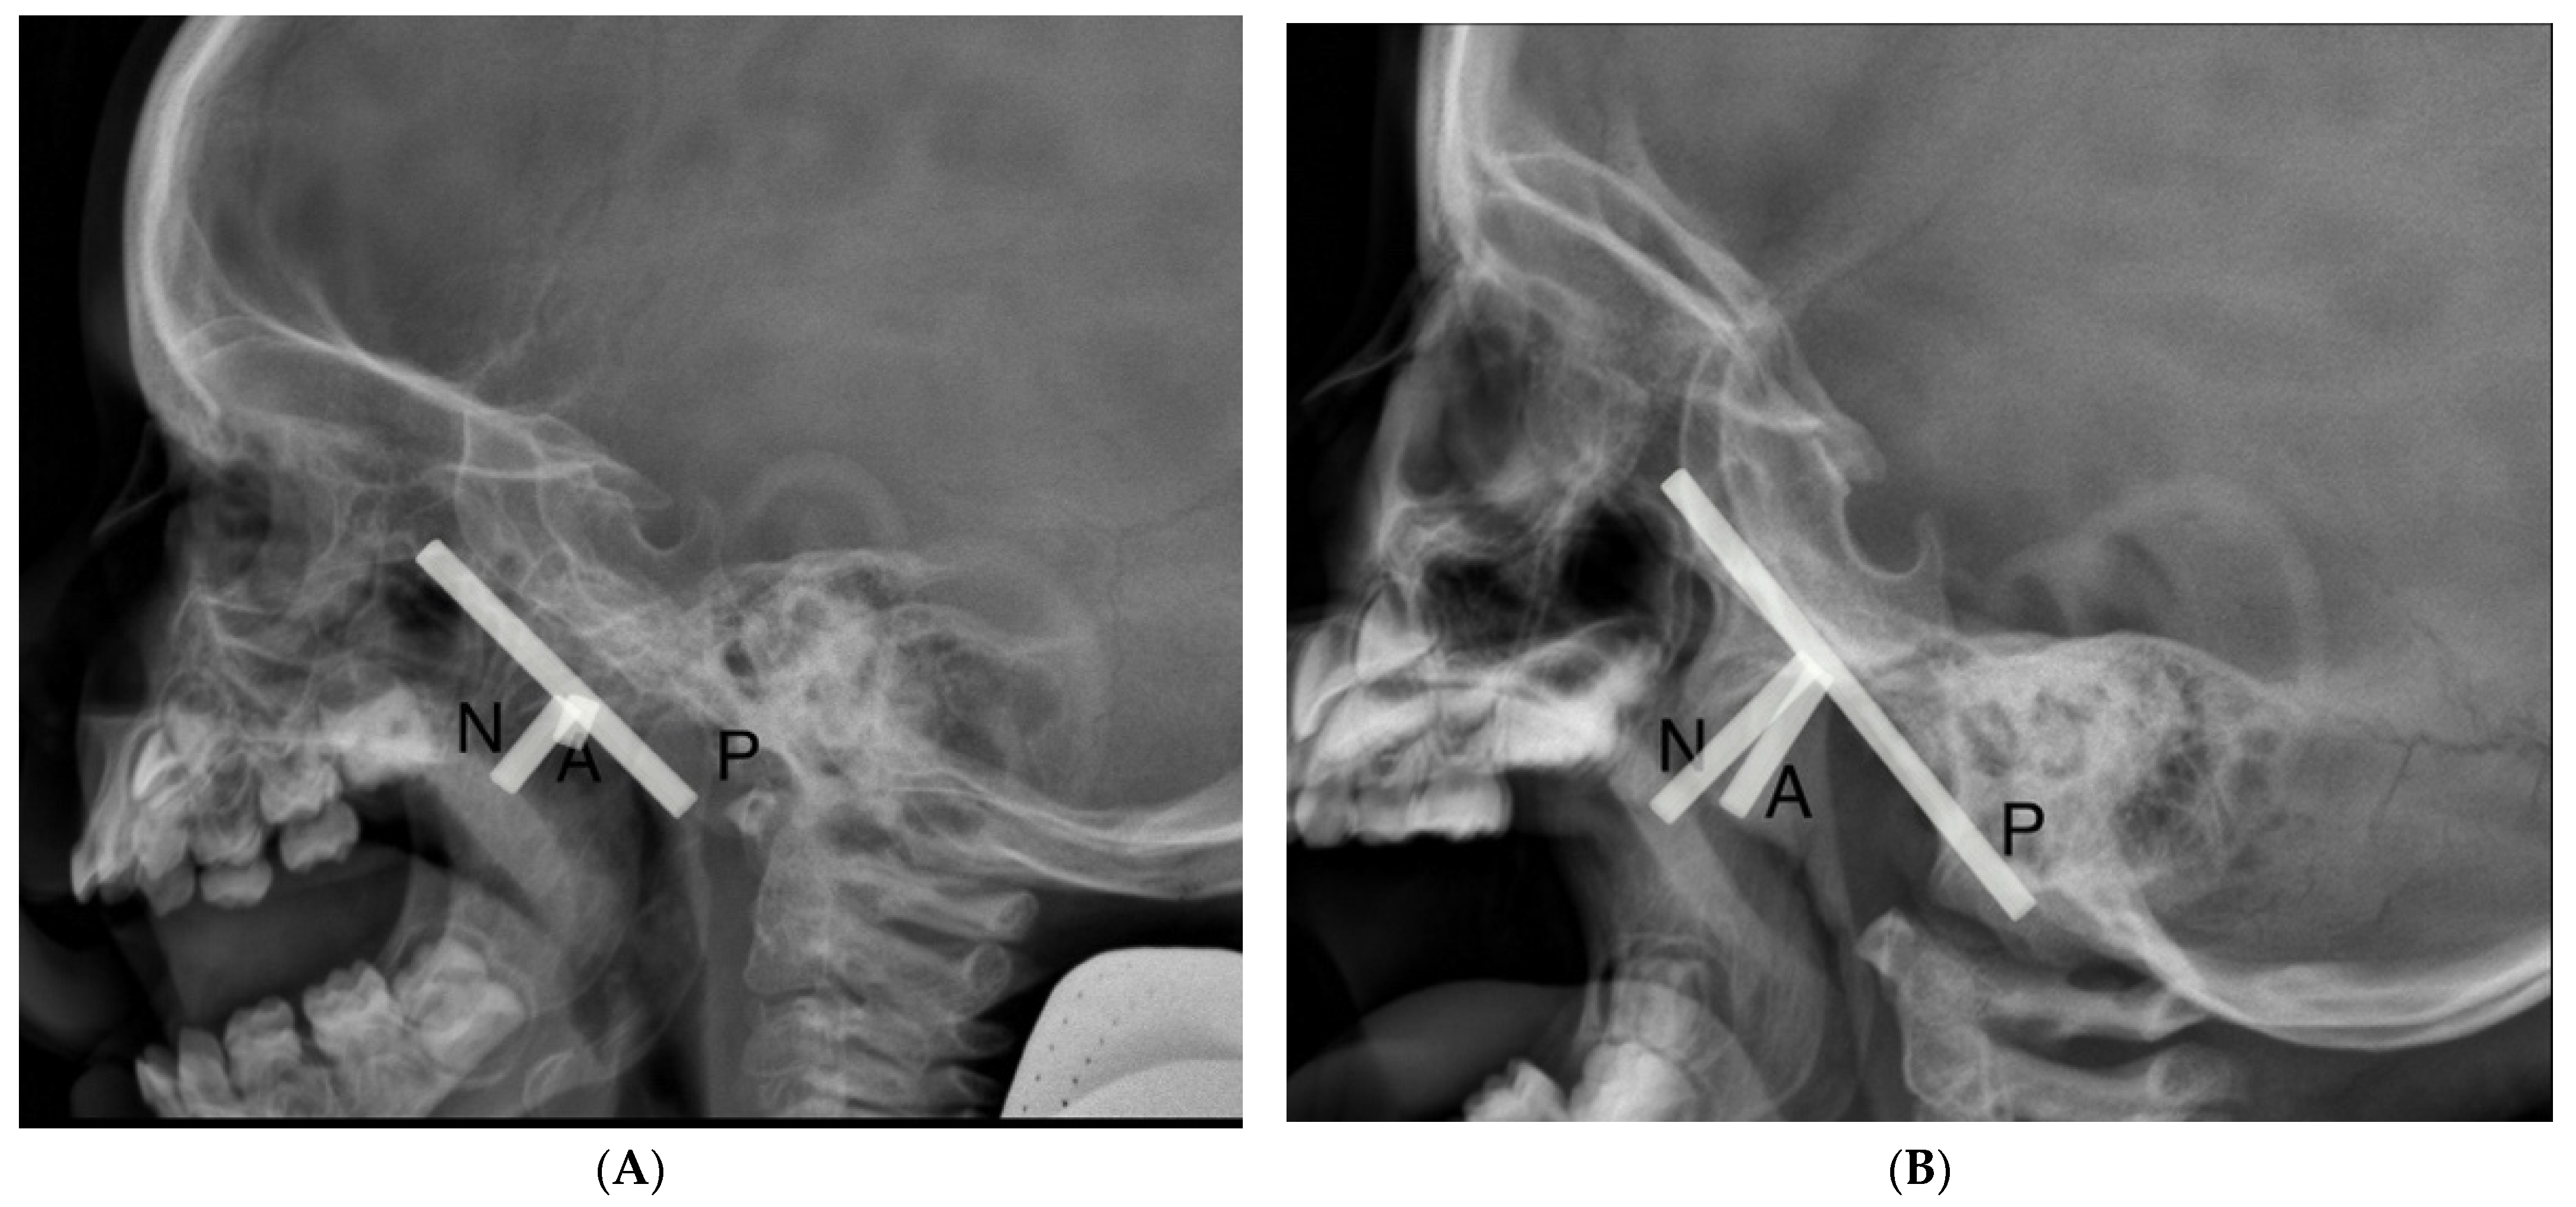

A total of 104 patients underwent flexible nasopharyngoscopy and 40 patients underwent lateral cephalometric X-ray exams. In Figure 1, we present lateral cephalometric X-ray findings, where the left side presents the nasopharynx of the patient without adenoid hypertrophy and the right side presents the nasopharynx with adenoid hypertrophy.

Figure 1.

Lateral cephalometric X-ray findings (A) nasopharynx without adenoid hypertrophy, (B) nasopharynx with adenoid hypertrophy. The adenoidal–nasopharyngeal ratio was calculated as the ratio of the distance between the outermost point of the anterior convexity of the adenoid shadow (A) and the straight part of the anterior margin of the basic occiput (P) to the distance between sphenobasioccipital synchondrosis and the posterior end of the hard palate (N).